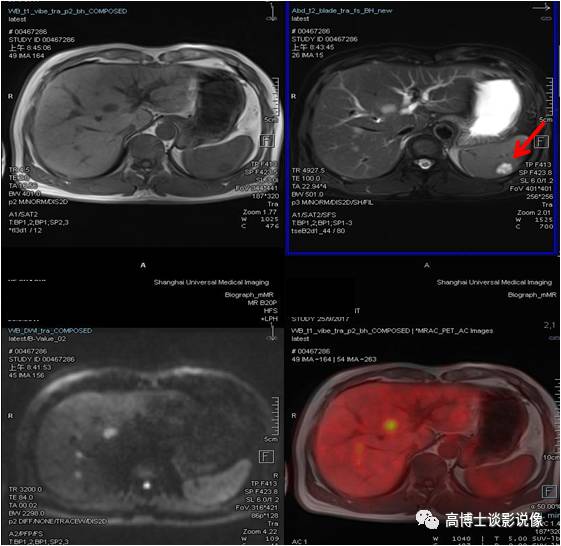

肾上腺腺瘤

中年男性,无任何症状。左侧肾上腺结合部见一长径约1.8cm结节,FDG稍摄取,考虑为肾上腺腺瘤。

点评

根据是否有功能,可分为无功能性和功能性腺瘤。一般来说,偶然发现的肾上腺腺瘤都是无功能性的。对于无功能性腺瘤,注意定期复查。功能性腺瘤需要专科医生进行评估,最好是具备诊断肾上腺肿瘤丰富经验的放射科医师、内分泌医生和外科医生组成的评估小组。